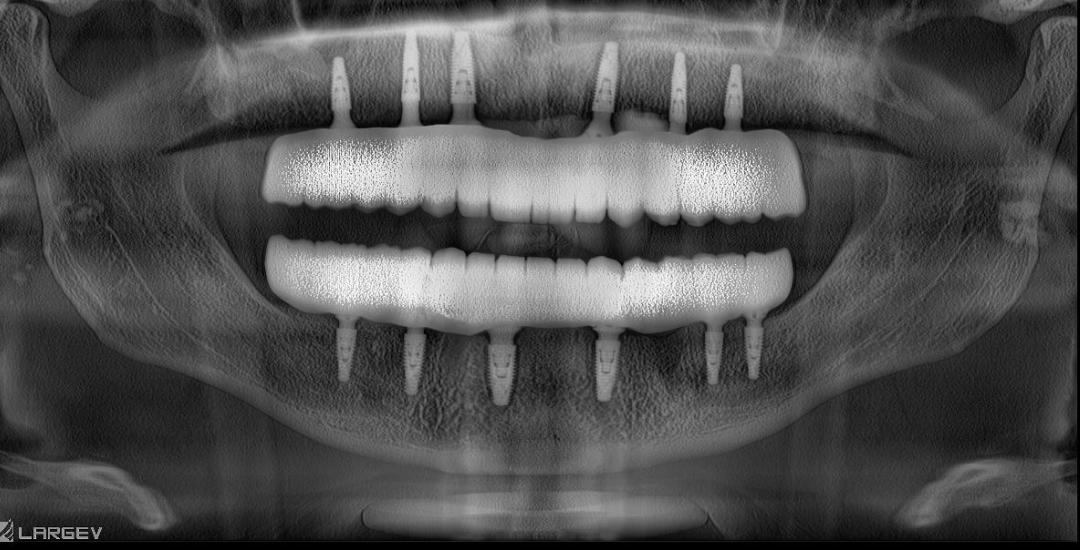

All-on-4 ve All-on-6 İmplant Sistemleri

Antalya’da All-on-4 ve All-on-6 implant tedavileriyle eksiksiz bir gülüş kazanın. Dr. Onur Ademhan ve Perla Dental Clinics, kalıcı estetik çözümler sunar.